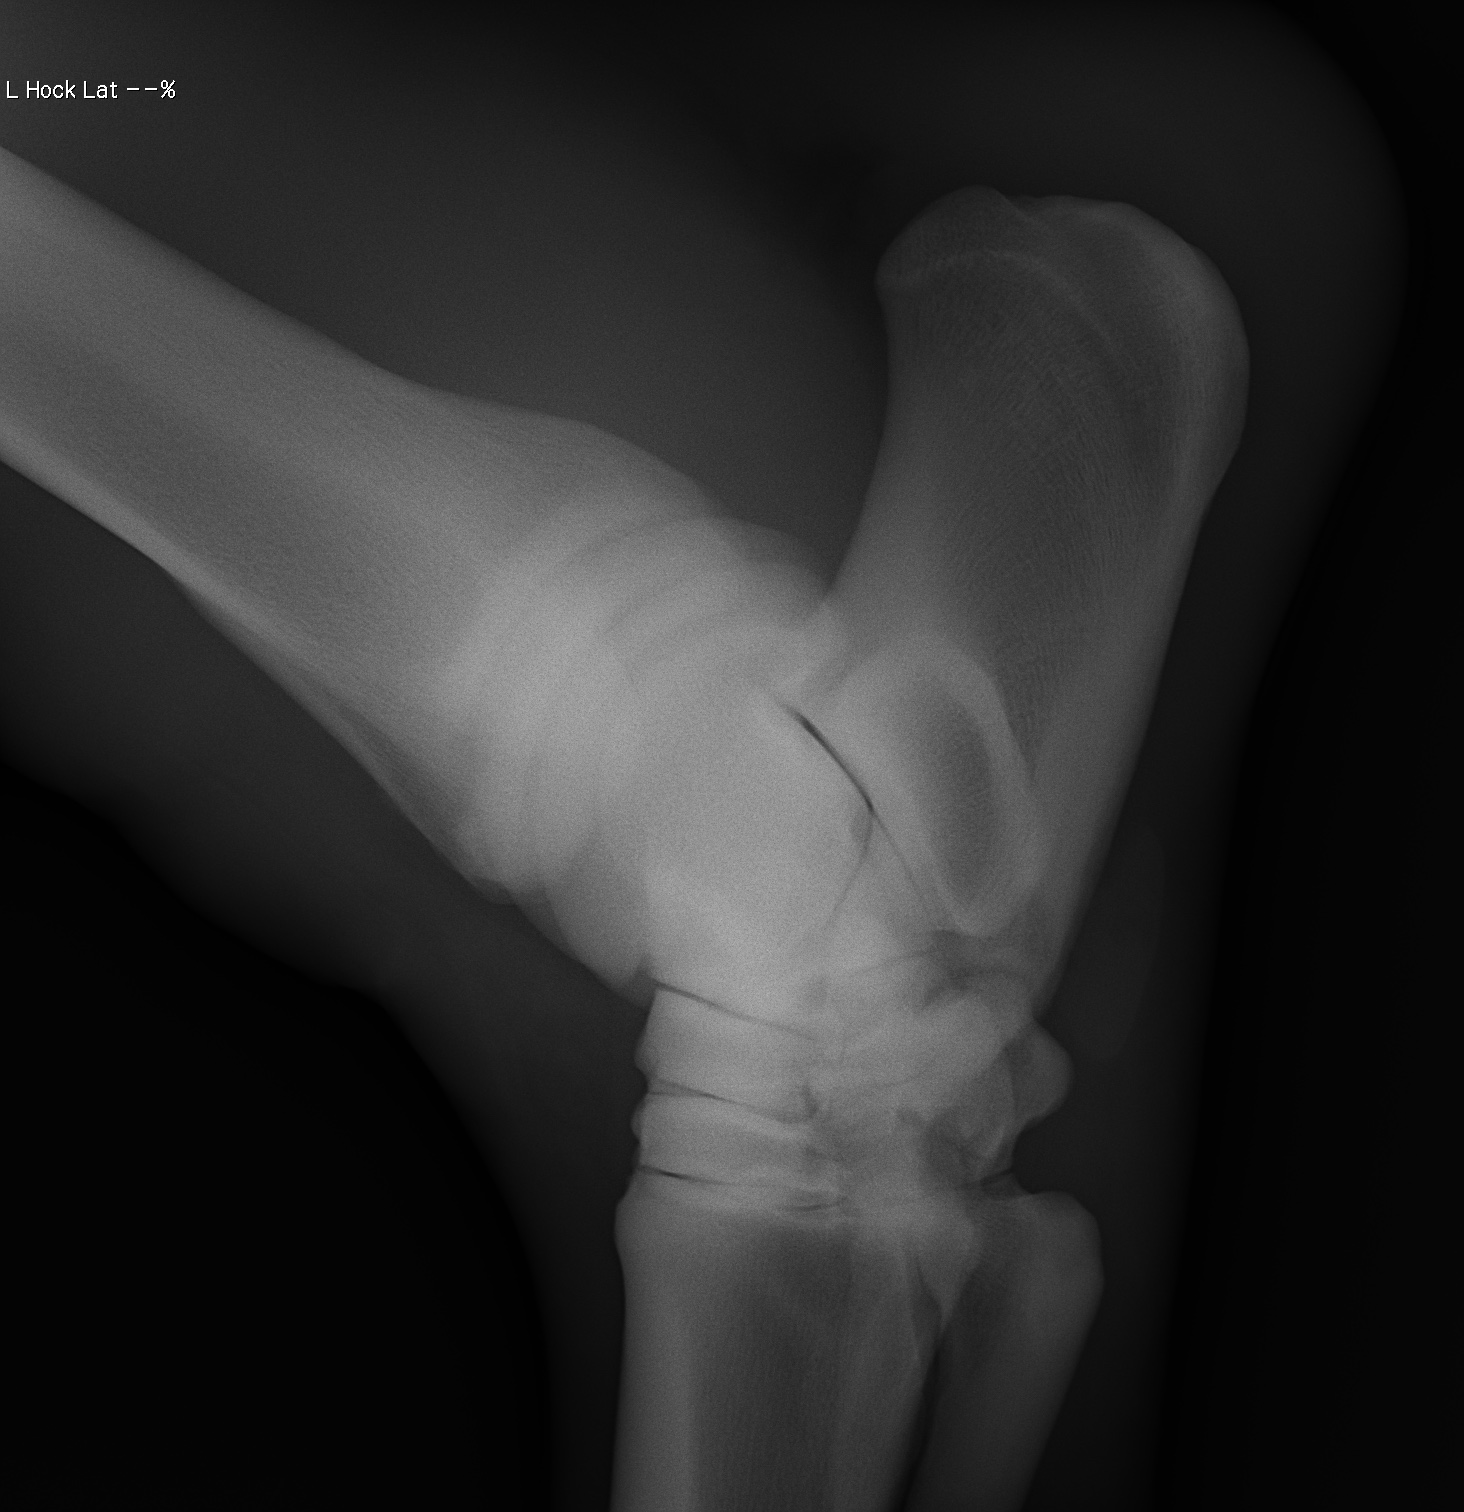

添付のレントゲン画像をご確認ください。現状渡しのノークレームノーリターンでお願いいたします。記載事項に関するキャンセルには応じられません。

※2022年12月17日の競走にて左後脛骨不全骨折を発症しています(全治6~9ヵ月)。